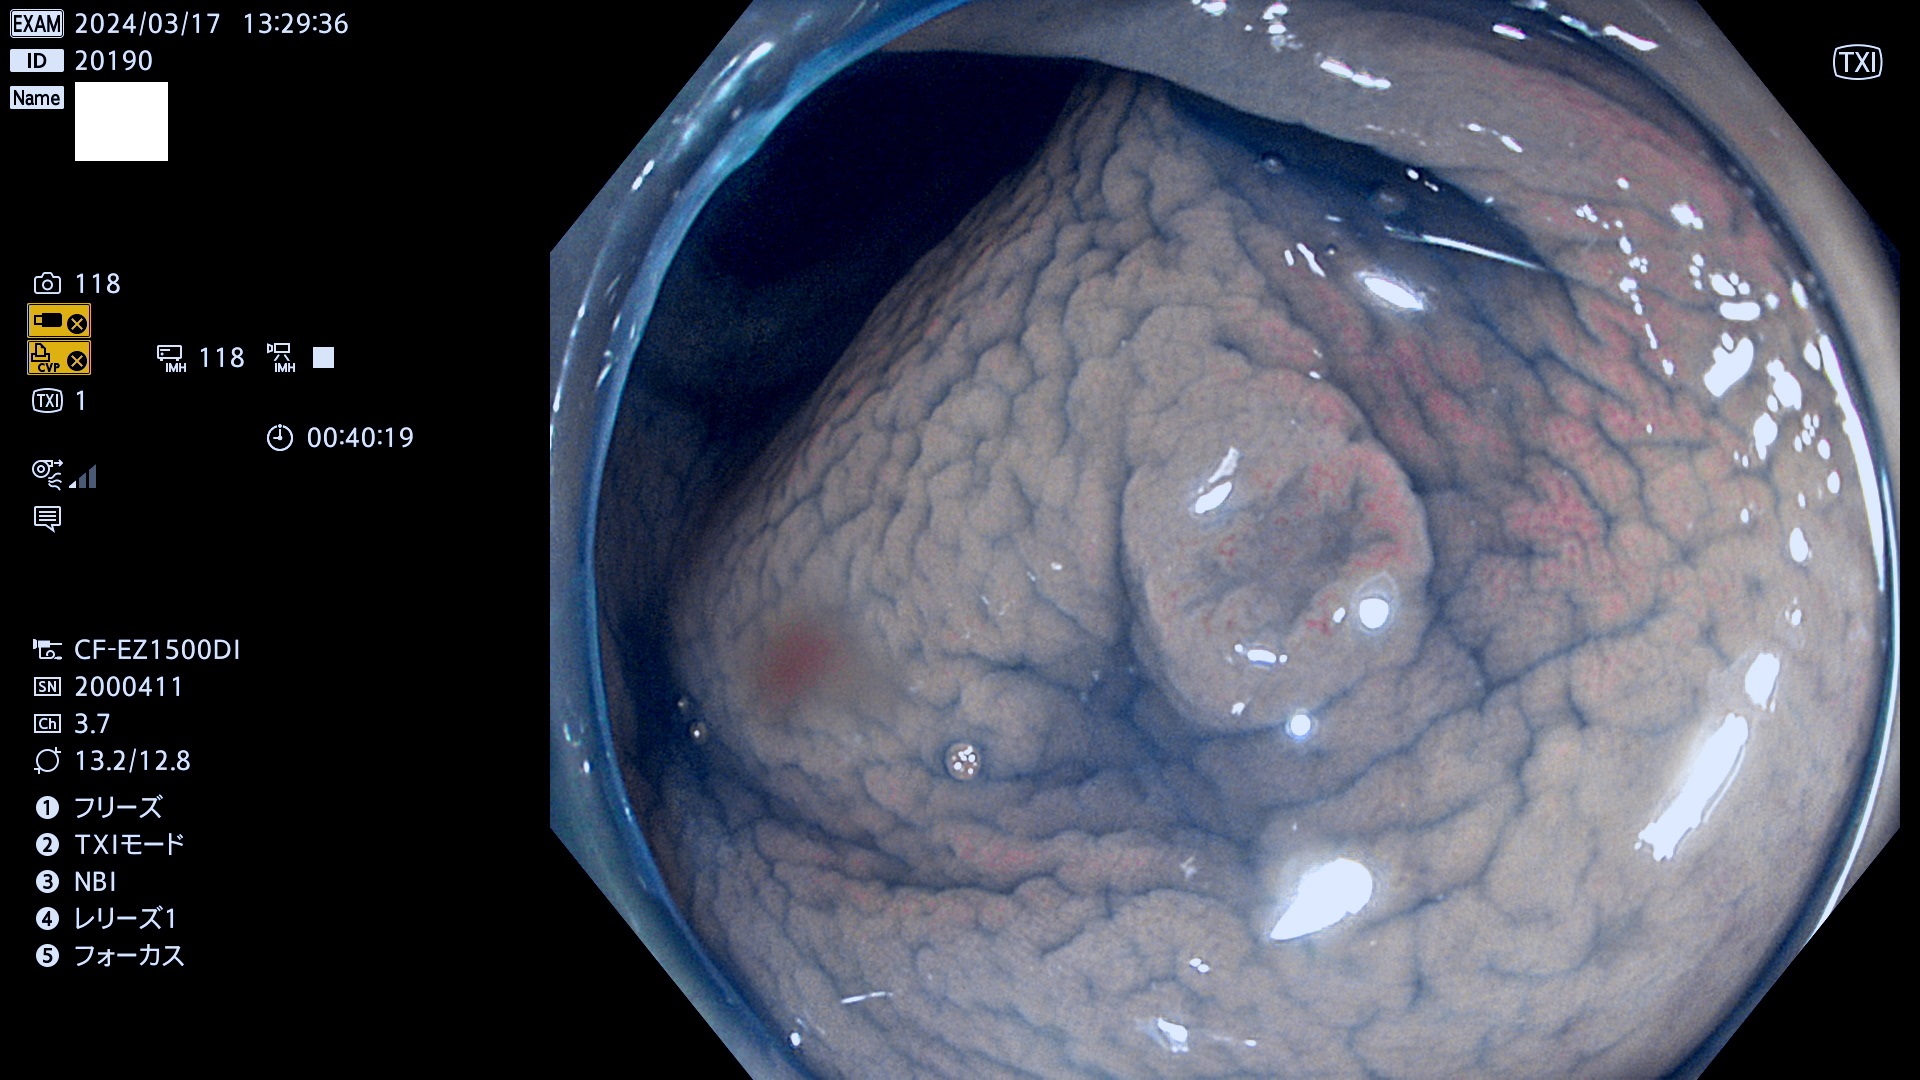

表面型腺腫(Flat Adenoma)の中で、完全に平坦な物をUb、陥凹している物をUcと呼びます。平坦隆起型(Ua)よりも、発見が難しく危険な病変です。

抽出の対象期間 2024年3月14日(木)〜3月18(月)の5日間(55件の検査)12件 (12/55=22%)